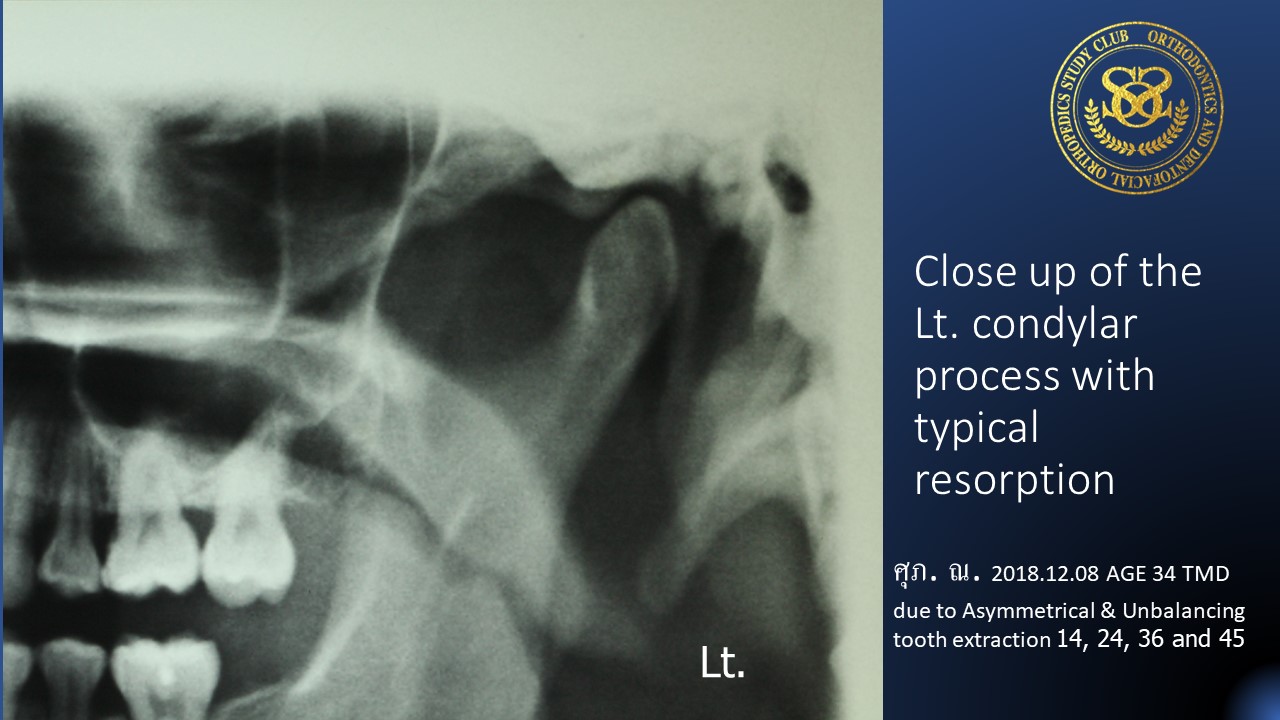

In this case the extraction pattern was 14, 24 , 36 and 45, which can never be a proper pattern, because it will send overloading to the TMJs - The rule of extraction was not taken into consideration and here are “Symmetrical and Balancing Extraction in the same segment”

- TMD is invited